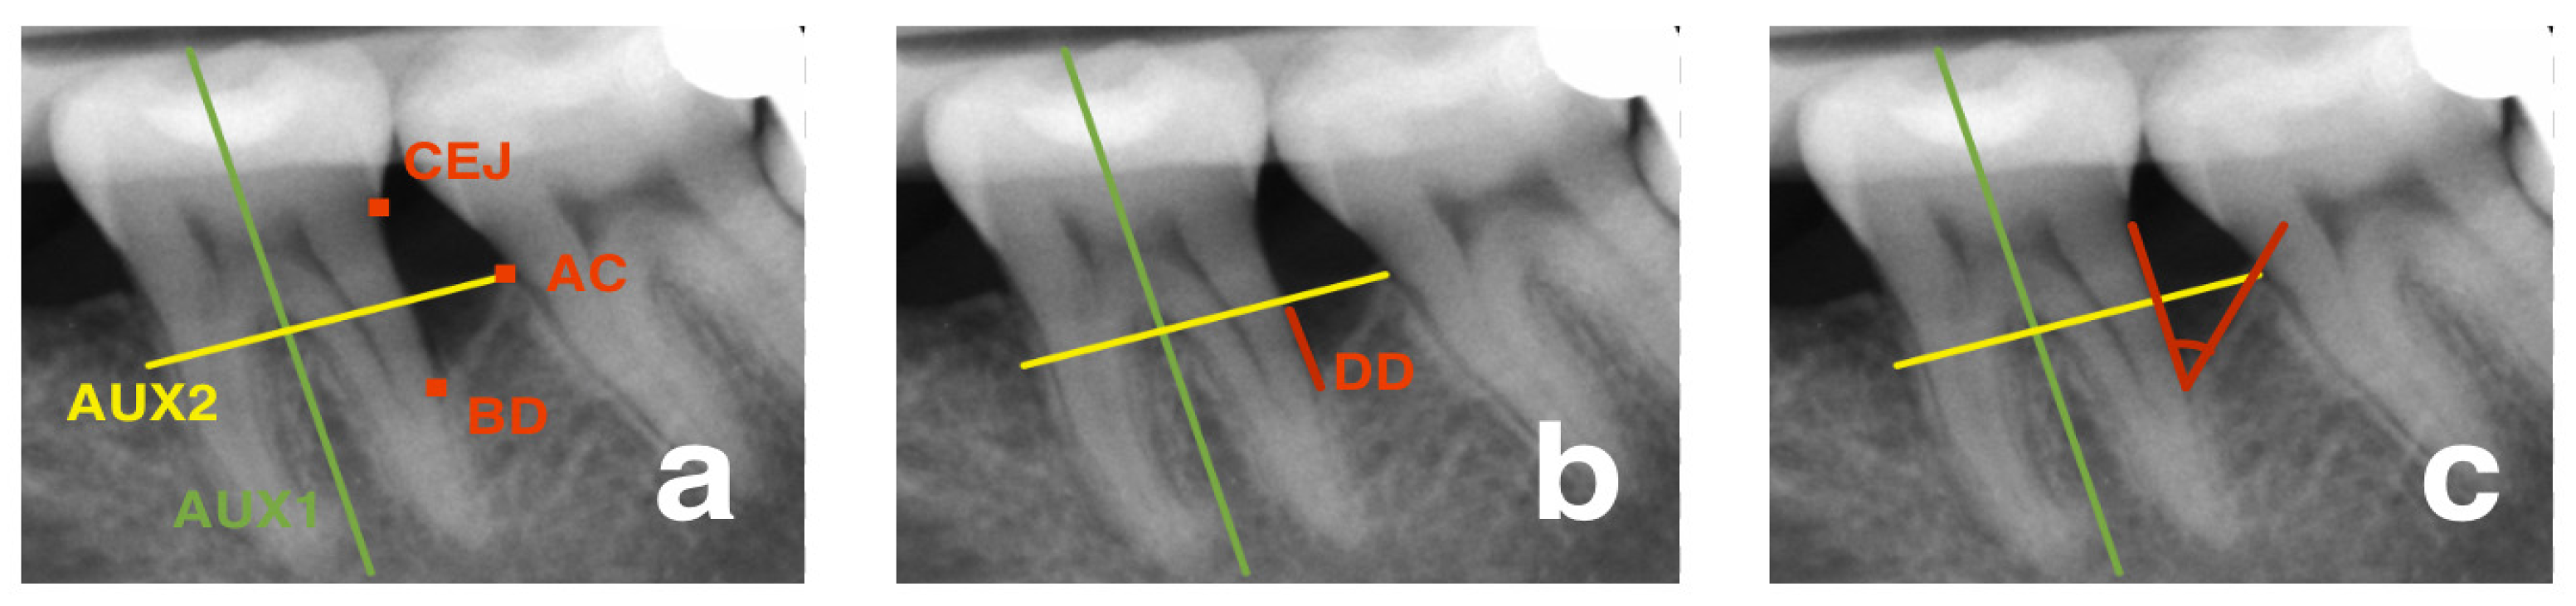

2.5. Radiological Outcomes

- Eickholz, P.; Hörr, T.; Klein, F.; Hassfeld, S.; Kim, T.S. Radiographic parameters for prognosis of periodontal healing of intrabony defects: Two different definitions of defect depth. J. Periodontol. 2004, 75, 399–407. [Google Scholar] [CrossRef] [PubMed]